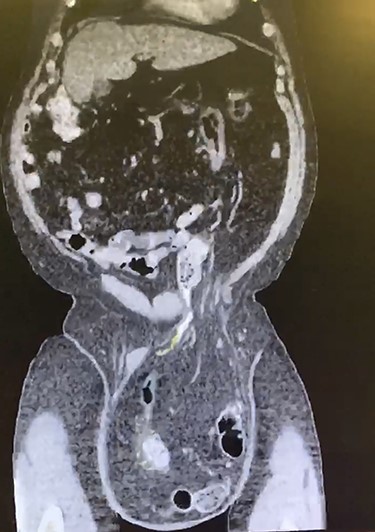

A 66-year-old male with a body mass index (BMI) of 36 presented to the clinic with a GIH of more than 10 years (Fig. 1). It has remained of similar size for the past 5 years and has caused discomfort but without frank pain. A chronically incarcerated umbilical hernia and small right inguinal hernia was also present on exam. Computed tomography (CT) scan showed large amounts of omentum, sigmoid colon, portions of transverse/descending colon and left ureter housed within the 5.7 L inguinoscrotal hernia sac (Figs 2 and 3). Additionally, the left ureter was tortuous and dilated, consequently causing moderate hydronephrosis. The patient was instructed to lose weight and undergo close follow-up in the outpatient setting for preoperative optimization of his preexisting medical conditions, hypertension and hypercholesteremia. He presented 9 months later with a BMI of 31, and an intra-peritoneal catheter was then placed to begin PPP. One liter of carbon dioxide per day was progressively insufflated for a total of 10 days. Concurrently, Deep vein thrombosis prophylaxis was initiated and continued throughout. Following pre-treatment of PPP, midline laparotomy hernia repair (Stoppa technique) was carried out. Manual reduction of incarcerated omentum and sigmoid colon were unsuccessful. Therefore, a counter longitudinal incision was made on the left scrotum, which allowed the sac to decompress for further ease of reduction. Moderate omentectomy was required to allow the delivery of residual omentum and sigmoid colon back into the abdominal cavity. Additionally, left orchiectomy was performed, given the high risk of potential torsion due to the lengthy and redundant pedicle residing in the new vacant hemiscrotum. With the contents fully reduced, a high amount of fascial tension remained. Thus, a bilateral TAR was proceeded in order to further assist in achieving a tension-free closure. Division of the transversus abdominis muscle fibers was attained by hydrodissection. Blunt dissection was then continued throughout the space of Bogros and the space of Retzius, both inferiorly and laterally. This allowed for the fascial layers to meet in the midline in a tension-free manner. Additionally, the small 3-cm right indirect inguinal hernia was identified and was sequentially reduced with an excision of a large cord lipoma. The hernia defects were closed and two 30 × 15 cm pro-grip meshes were placed in a preperitoneal fashion, laying over the myopectineal orifices bilaterally (Stoppa technique). The patient had an additional umbilical defect which was reduced and repaired using an additional piece of 30 × 15 cm pro-grip mesh, oriented cephalocaudally and placed in the retrorectus space for additional ventral support. The scrotal skin was left intact to allow for possible future scrotal reconstruction. The patient was extubated without respiratory complications and discharged home comfortably after an uncomplicated 7-day hospital stay. The patient required left scrotal seroma drainage 2 months postop, which consequently required the excision of the multiloculated cystic collection in the following month. Follow-up ensued once every 2 weeks to ensure optimal wound healing.

Coronal CT displaying sigmoid colon and accompanying abdominal contents traversing into the hernia sac.